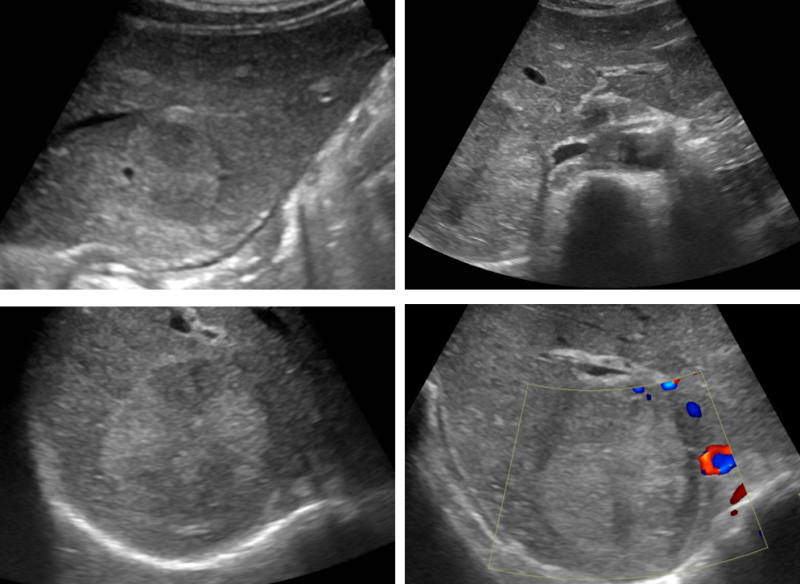

A patient in his 20s came to the hospital because of discomfort and a mass of seeds on his right neck. The patient complained that he had no cold symptoms such as sore throat, and that he felt a little tired. During the examination, a tumor slightly larger than the thumb was touched on the upper part of the collarbone on the right side, and neck ultrasound was performed to distinguish lymph node disease.In the cervical ultrasound, a number of atypical lymphadenoma bands were observed in the upper right clavicle, and lymph node enlargement of up to 3.8 cm was observed. Loss of lymph nodes in the center of the lymph node and irregular ultrasound shadow inside were observed, and there was a possibility of lymphatic tumor. Additionally, CT examinations also found that many lymph node hypertrophy and lymph tumors were suspected, and I transferred to a tertiary hospital to distinguish lymph tumors. I had an incision biopsy at the third hospital, and after a tissue examination, I was diagnosed with lymphatic cancer and received anti-cancer treatment, and now I’m fully recovered and doing well.

cervical lymphadenoma band

Neck ultrasound examination, famous internal medicine in Pungam-dong